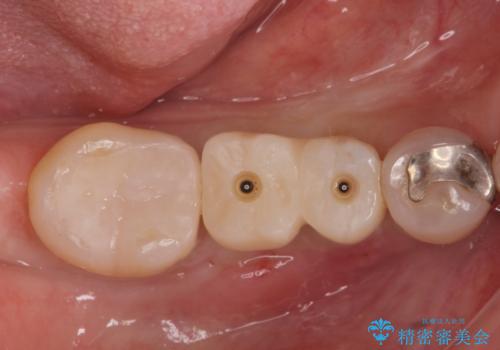

無事インプラントが入りました。

欠損部に1本だけインプラントを埋入しても大きな被せ物になってしまい清掃性が悪くなるので清掃性が良くなるように2本小臼歯用のインプラントを埋入しました。

また1番奥の歯はセラミックインレーで治療を行いました。